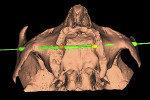

The digital imaging and communications in medicine (DICOM) data from the 3D scan first is exported from the imaging device and then imported into the implant planning software. Through the use of the diagnostic tools within the software, the entire maxillary anatomy is studied for any anatomical variations, density, topography of the maxillary sinus, and potential pathology. Consequently, the alveolar bone and zygomatic bone are evaluated for receptor sites that may be most suitable for insertion of the zygomatic implants. The simulation for the implant placement is used to define the entrance point, trajectory path (implant path), and exit point of the implants (Figure 1 and Figure 2).

As with conventional guided implant planning, there is not one view that contains enough information for definitive planning. Therefore, clinicians must utilize both the 3D and 2D views in the various spatial planes, depending on the software application used. These include coronal, axial, panoramic, cross-sectional, and sagittal oblique.